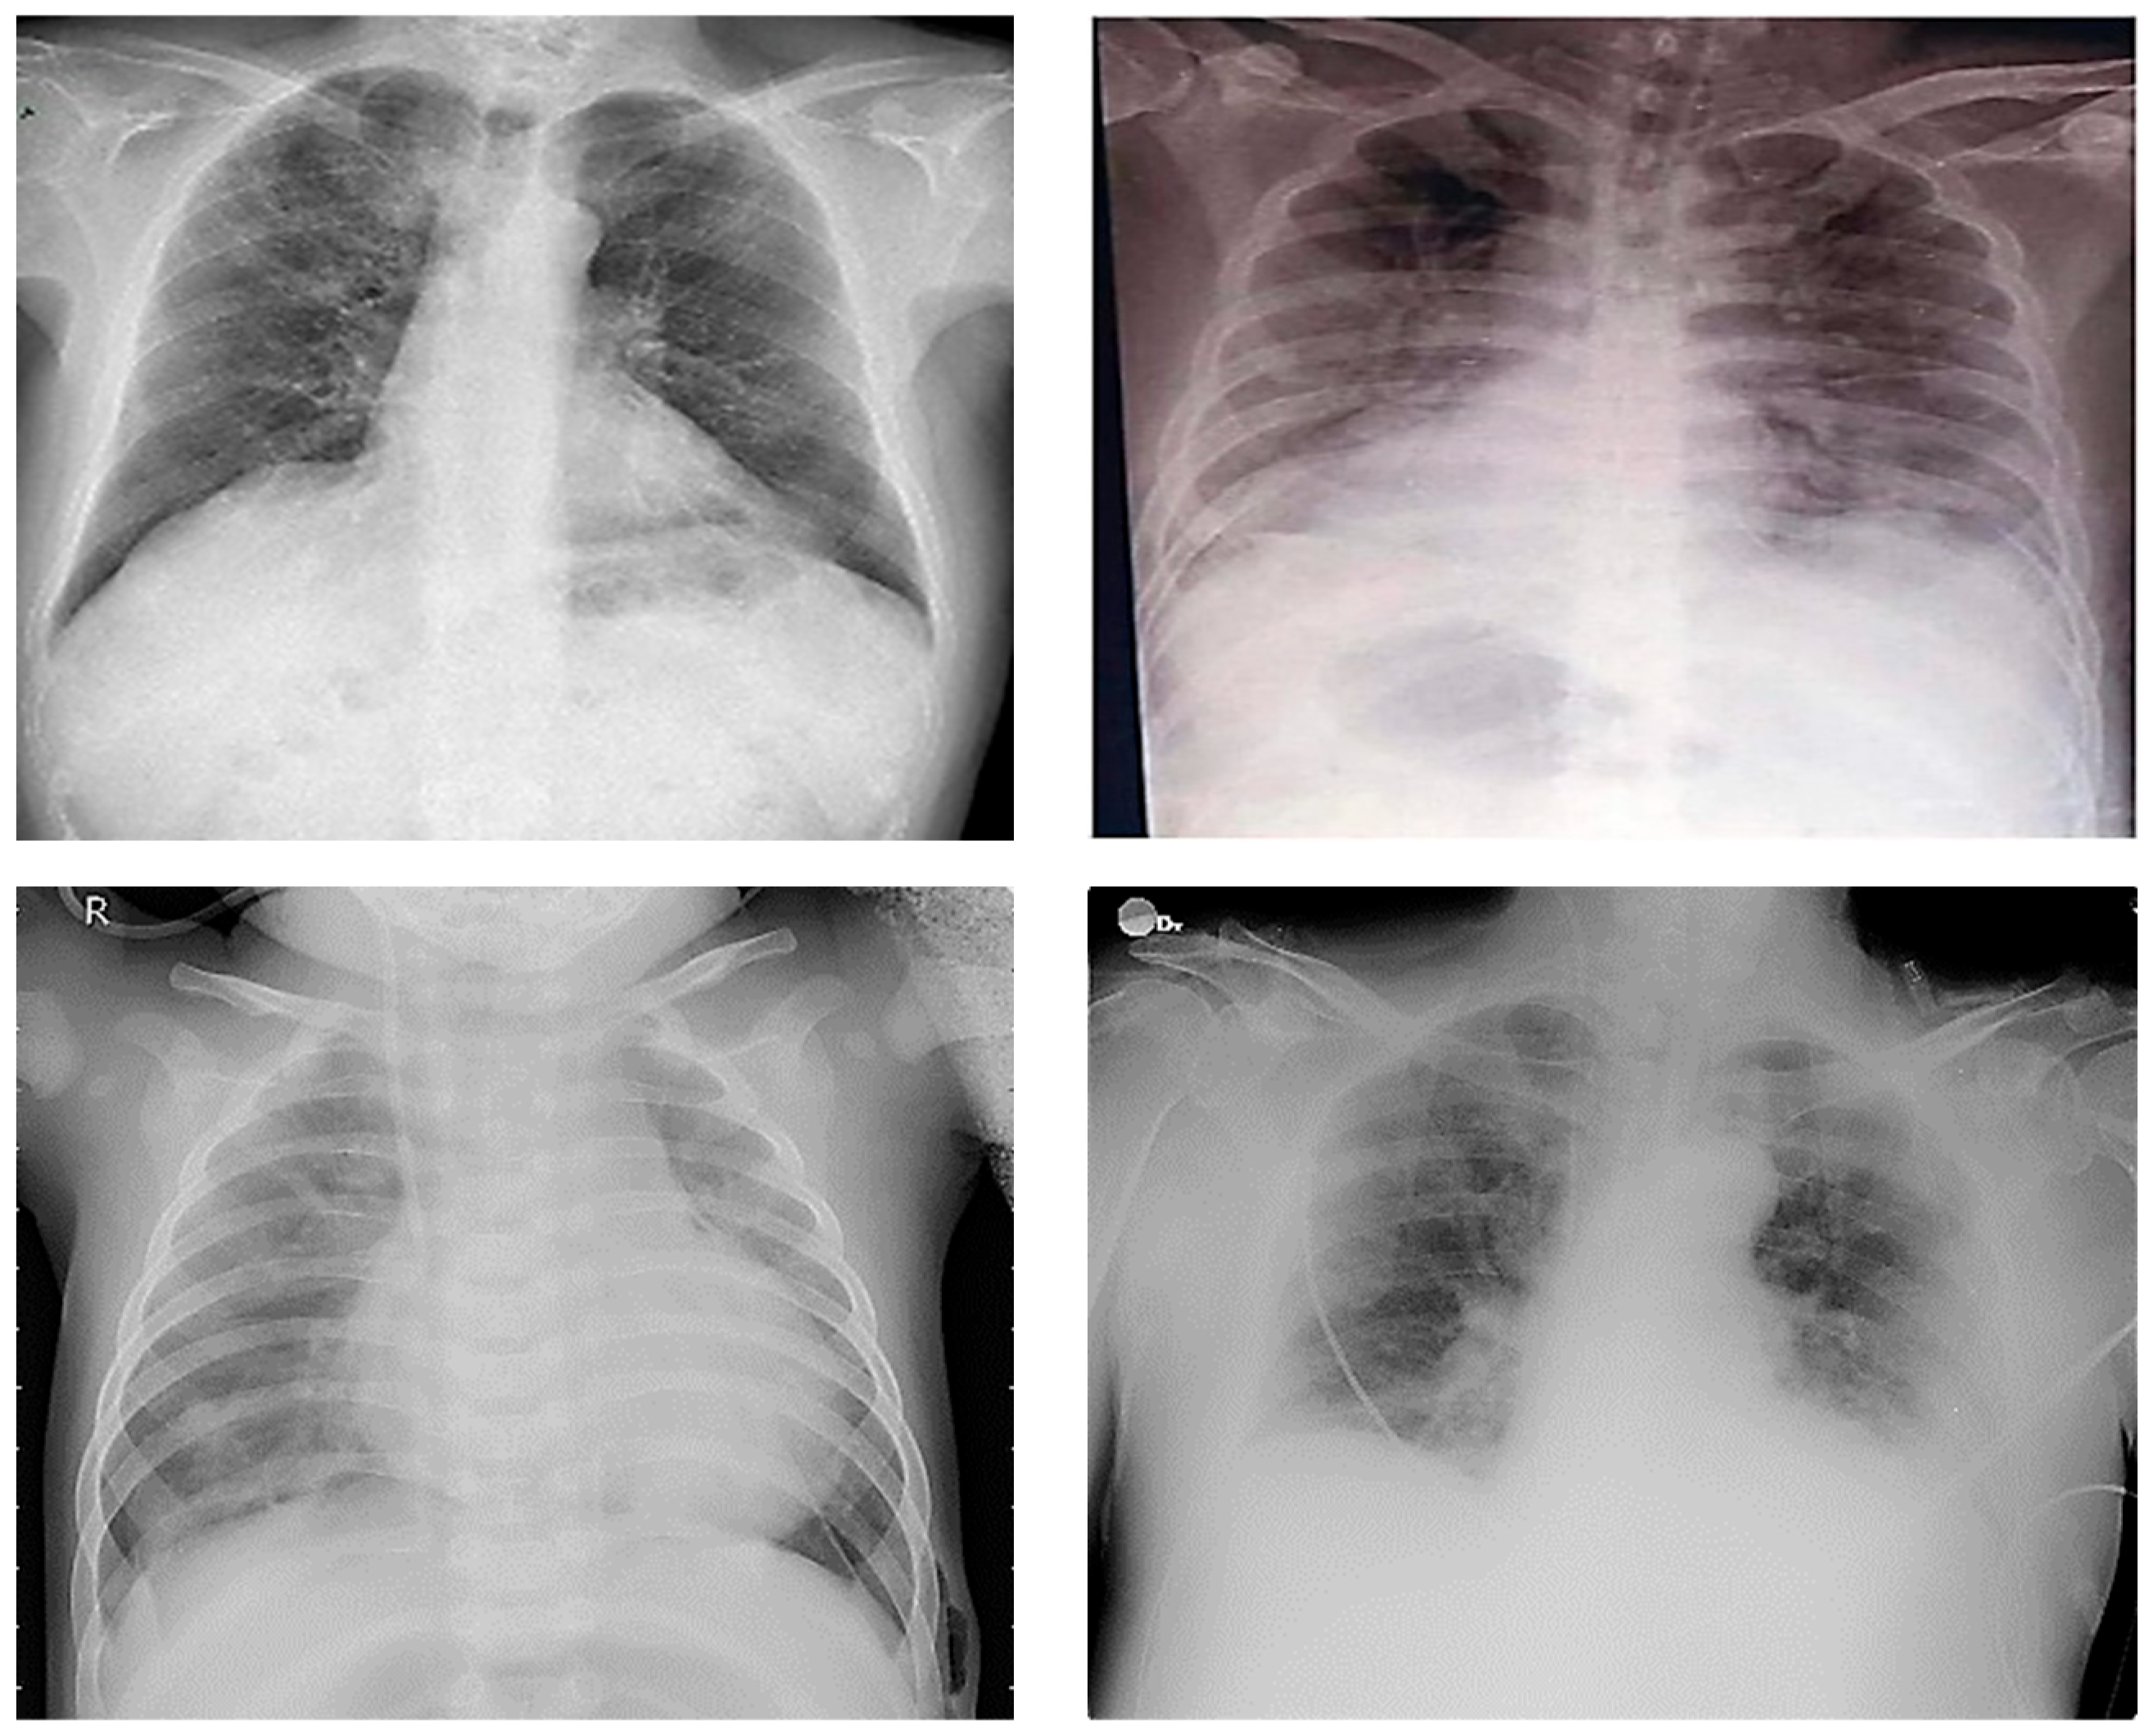

- Ground glass opacities and consolidation;

- Parenchymal abnormalities;

- Interstitial changes;

- Peripheral ground glass opacities;

- Vascular congestion signs;

- Pleural effusion.